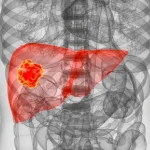

پیشگیری از سرطان کبد میتواند یکی از بهترین روشهای حفظ و سلامتی بیماران باشد. سرطان کبد یکی از بیماری هایی است که با علائم خاموش بروز پیدا میکند و ممکن است تا سالها ناشناخته باقی بماند و معمولا درمان آن بسیار سخت خواهد بود. به همین دلیل است که پیشگیری از ابتلا به این سرطان بسیار آسانتر و هوشمندانه تر از درمان آن خواهد بود. در این مقاله مهمترین نکات و توصیهها برای جلوگیری از سرطان سینه را با هم بررسی خواهیم کرد. همچنین اگر سوالی درباره این موضوع دارید، میتوانید به صورت آنلاین از متخصص بپرسید. با ما همراه باشید.

چرا پیشگیری از سرطان کبد اهمیت دارد؟

سرطان کبد یکی از کشنده ترین سرطانها در جهان به شمار میآید. طبق آمار سازمان جهانی بهداشت (WHO)، این بیماری در رتبه ششم سرطانهای شایع و در رتبه سوم علل مرگ ناشی از سرطان قرار دارد. نکته نگرانکننده اینجاست که اغلب بیماران زمانی متوجه بیماری خود میشوند که سرطان در مراحل پیشرفته است و شانس درمان موثر کاهش پیدا کرده است.

سرطان کبد اغلب به صورت مستقیم به وجود نمیآید، بلکه نتیجه بیماریهای مزمن و آسیبهای طولانی مدت به بافت کبد است. بنابراین درمان سرطان کبد بسته به ریشه و دلیل آن خواهد داشت. برخی بیماریهای زمینهای مهم که خطر ابتلا به این سرطان را افزایش میدهند، عبارتاند از: